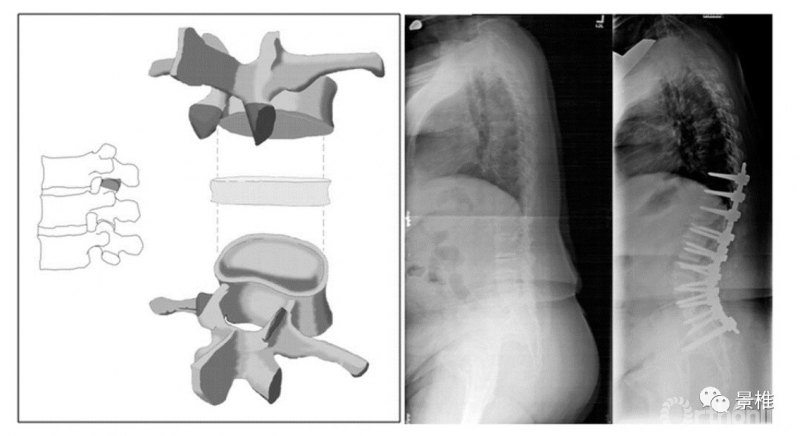

2级 Ponte

2级,除了关节突,再多凿掉一部分,椎板和黄韧带都切除。典型术式是Ponte截骨。

Ponte截骨是Ponte于1987年发表,完全切除胸椎关节突和部分椎板、全部黄韧带的术式,用于治疗胸椎后凸畸形。

最初的Ponte截骨是关节突全部切除、部分椎板的V型切除。

后来逐渐扩大范围,可以做到椎弓根-椎弓根间的椎板和关节突全切除。后凸矫形平均可达30º左右。

1、2级截骨切除的都是椎体后方结构,也叫PCO(后柱截骨术)。